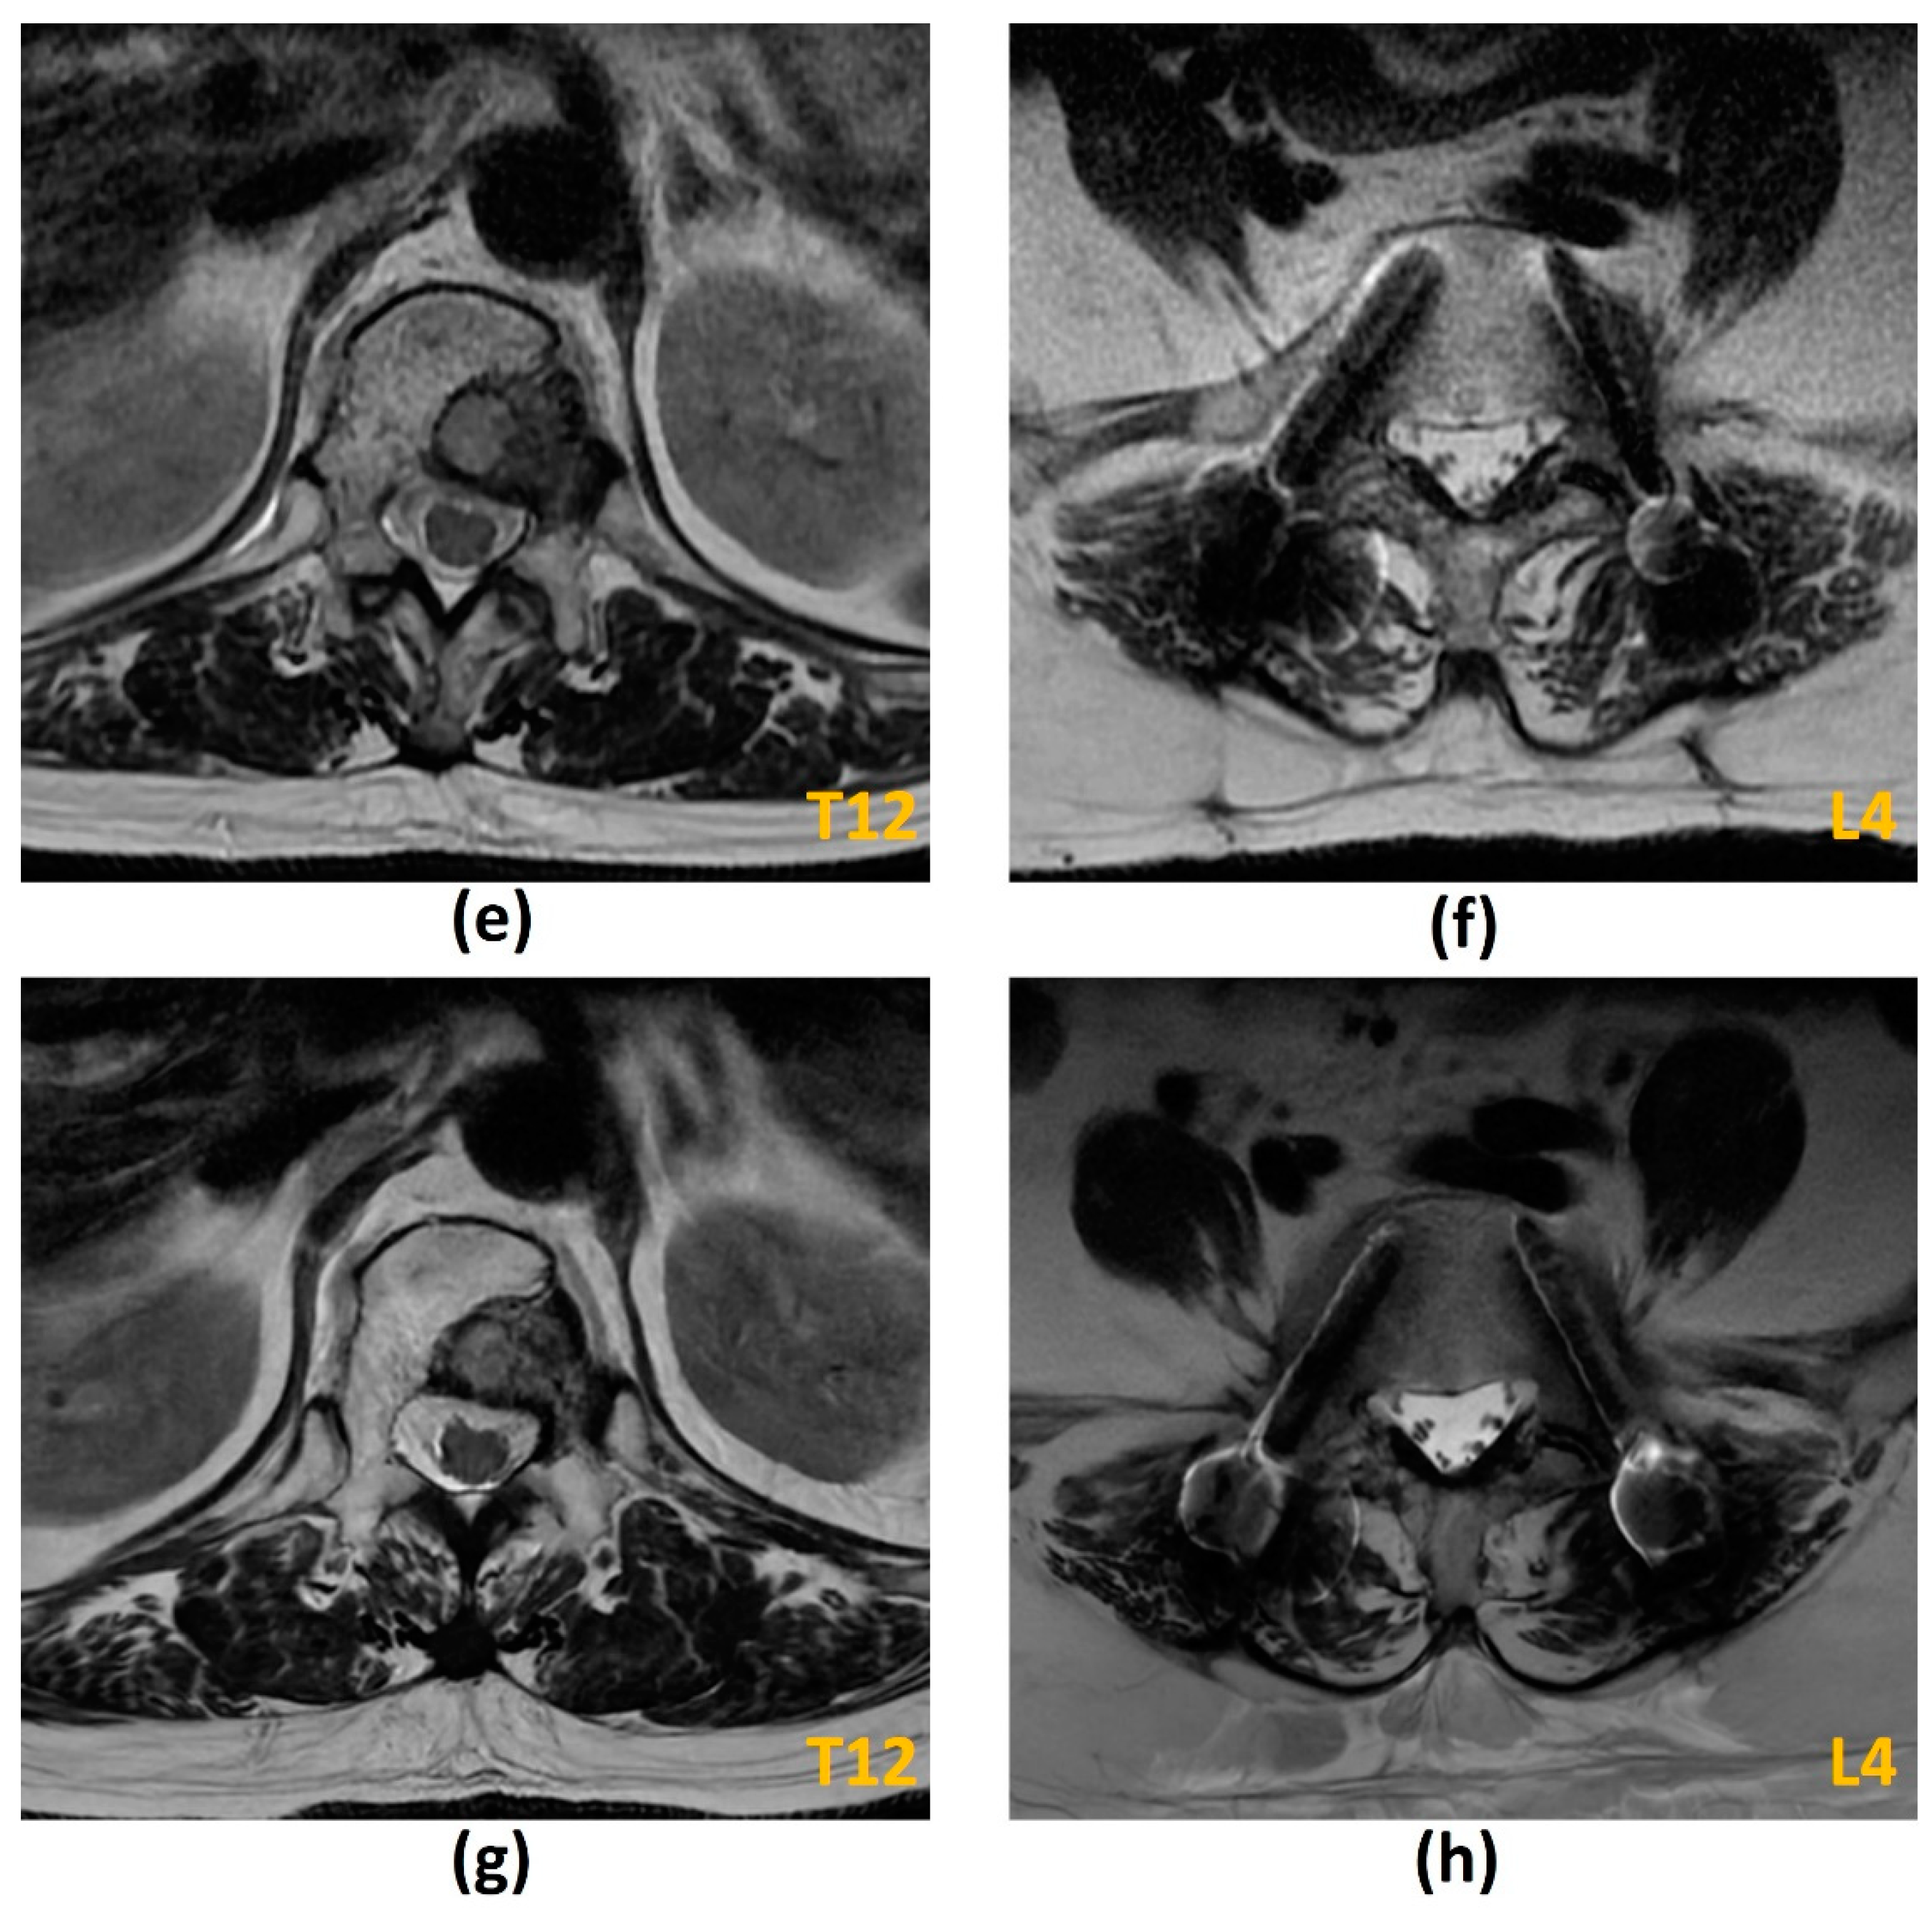

- Krätzig, T.; Mende, K.C.; Mohme, M.; Kniep, H.; Dreimann, M.; Stangenberg, M.; Westphal, M.; Gauer, T.; Eicker, S.O. Carbon fiber-reinforced PEEK versus titanium implants: An in vitro comparison of susceptibility artifacts in CT and MR imaging. Neurosurg. Rev. 2021, 44, 2163–2170. [Google Scholar] [CrossRef]

- Kumar, N.; Lopez, K.G.; Alathur Ramakrishnan, S.; Hallinan, J.T.P.D.; Fuh, J.Y.H.; Pandita, N.; Madhu, S.; Kumar, A.; Benneker, L.M.; Vellayappan, B.A. Evolution of materials for implants in metastatic spine disease till date—Have we found an ideal material? Radiother Oncol. 2021, 163, 93–104. [Google Scholar] [CrossRef] [PubMed]

- Kumar, N.; Ramakrishnan, S.A.; Lopez, K.G.; Madhu, S.; Ramos, M.R.D.; Fuh, J.Y.H.; Hallinan, J.; Nolan, C.P.; Benneker, L.M.; Vellayappan, B.A. Can Polyether Ether Ketone Dethrone Titanium as the Choice Implant Material for Metastatic Spine Tumor Surgery? World Neurosurg. 2021, 148, 94–109. [Google Scholar] [CrossRef] [PubMed]

- Osterhoff, G.; Huber, F.A.; Graf, L.C.; Erdlen, F.; Pape, H.C.; Sprengel, K.; Guggenberger, R. Comparison of metal artifact reduction techniques in magnetic resonance imaging of carbon-reinforced PEEK and titanium spinal implants. Acta Radiol. 2021, 2841851211029077. [Google Scholar] [CrossRef]